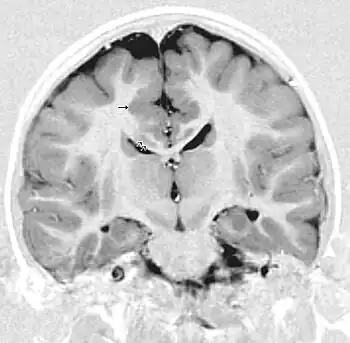

MRI of a child experiencing seizures. There are small foci of grey matter heterotopia in the corpus callosum, deep to the dysplastic cortex. (double arrows)

Gray matter heterotopia is a neurological disorder caused by gray matter being located in an atypical location in the brain.[1] Grey matter heterotopia is characterized as a type of focal cortical dysplasia. The neurons in heterotopia are otherwise healthy; nuclear studies have shown glucose metabolism equal to that of normally positioned gray matter.[2] The condition causes a variety of symptoms, but usually includes some degree of epilepsy or recurring seizures, and often affects the brain's ability to function.